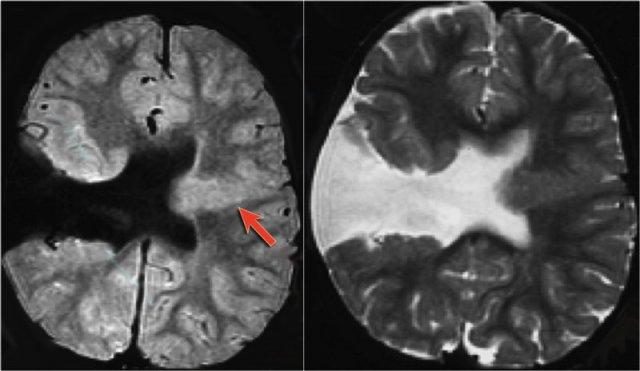

FLAIR axial, DWI axial và T2W coronal cho thấy hải mã tăng tín hiệu với sừng thái dương của não thất bên bị thu hẹp nhẹ, phù hợp với phù nề hải mã.

DWI cho thấy hạn chế khuếch tán do phù nề độc tế bào trong giai đoạn cấp tính của trạng thái động kinh liên tục.

DNET bắt chước xơ cứng thùy thái dương trong

T2W axial cho thấy hải mã tăng tín hiệu nhưng phì đại với hình ảnh dạng bong bóng.

Đây là hình ảnh điển hình của DNET hay u thần kinh biểu mô loạn sản phôi thai, sẽ được thảo luận chi tiết ở phần tiếp theo.

T1W coronal sau tiêm thuốc tương phản từ cho thấy hải mã phì đại không ngấm thuốc tương phản từ.